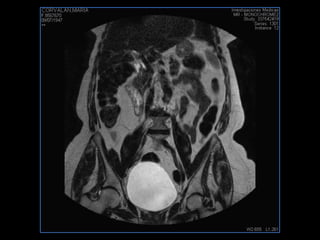

PROTOCOLO pelvis SAG T2, Y FAT SAT (FINOS) AXIAL T1  AX FAT SAT CON   GADOLINIO :  AX T1 Y COR T1 SAT: NO  FASE: RL THK: 3MM  COIL:  GAP: (FACTOR 1.4) 1MM FOV: 40 CM NEX:2 SINCRONIZACION RESPIRATORIA EN 3 O 4 CICLOS ALE